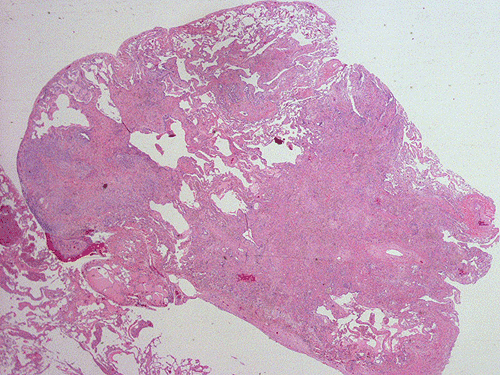

At scanning magnification (Panel A), the lung parenchyma is replaced by some coalescing fibrous nodules. The degree of involvement is variable at different fragments (Panel B and C). In the less affected areas, there are some fibrotic thickening of the septa (Panel C). In some areas, the changes are minimal and the pleural appear to be uninvolved (Panel D and E). In low to medium magnifications, these nodules of fibrosis contains a large number of hemosiderin laden macrophages (Panel F and G) admixed with fibrous tissue. The diagnostic tissue, however, is present in areas with increased cellularity. In these areas, there is a background of cells with a moderate amount of cytoplasm and bland nuclei. Some of these nuclei have kidney shape (arrow in Panel H). In some areas, many of the nuclei have a deep nuclear groove that resemble a coffee bean (arrow in Panel I). In the third type of areas, the nuclear grooving is not distinct (Panel J). Prominent eosinophilic infiltrations are almost always present. Immunohistochemistry on CD1a revealed many positive cells (Panel L). Also present in the specimen are multiple small blood vessels with thickened intima (Panel K). A Movat pentachrome stain demonstrates an internal elastic layer in these vessels and confirms that these are arteries (Panel M and N).

In the early stage of PLCH, there are interstitial infiltrates composed of LCs, lymphocytes, macrophages, eosinophils, plasma cells and fibroblasts 4. The infiltrates enlarge to form nodules centered on the small airways. Brown pigmented macrophages (smokers macrophages) are present in and around the nodules. Eosinophils tend to localize at the innermost layer of the nodules, where LCs can be most easily found in the thickened interstitium. Associated patchy interstitial and airspace organization or respiratory bronchiolitis may be present. Other smoking related changes are also common. Cavitation often occurs within the nodules which represents either an airway remenant or de novo cavitation as the inflammatory infiltrate enlarges. There is centripetal replacement of the nodules by fibroblasts which produce the classic stellate lesions of PLCH. As the disease progresses, the number of nodules, cavitary granulomas and fibrotic scars increase in number.

In the end stage, the exhausted lesions are predominantly fibrotic and largely depleted of LCs. In some regions, the fibrosis may surround cystic spaces of variable diameter to form large areas of honeycombing. This is especially predominant in the upper lobes. In cases where parenchymal scaring is present, the pulmonary function will be largely compromised. At this stage, both pulmonary function tests and radiologic findings may suggest diffuse lung disease, but biopsy will show stellate fibrotic lesions centered on the terminal airways with no identifiable interstitial inflammation. Pulmonary vasculopathy (in areas of lung remote from parenchymal nodules) is also seen in late stage PLCH. Vasculopathy manifests as intimal fibrosis, medial hypertrophy or luminal obliteration involving both venules and arteries. This may account for pulmonary hypertension seen late in PLCH.